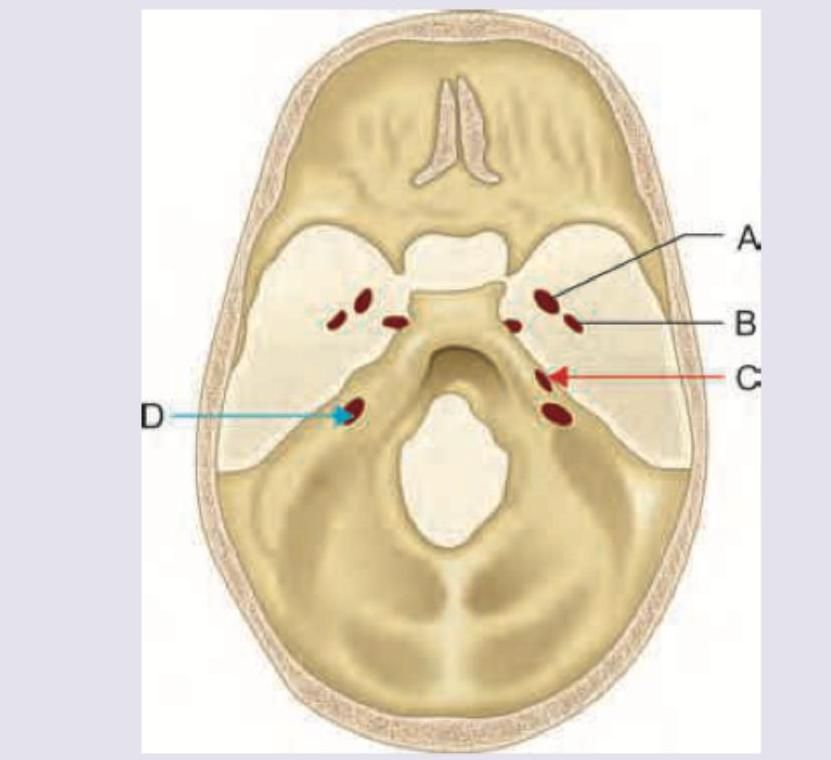

Match the following: A) Glossopharyngeal nerve B) Spinal accessory nerve C) Facial nerve D) Mandibular nerve 1) Shrugging of shoulder 2) Touch sensation from the posterior one-third of the tongue 3) Chewing 4) Taste from the anterior two-thirds of the tongue

Mandibular division of trigeminal nerve passes through which of the following? (AIIMS May 2018)

Explanation: ***A-2 , B-1 , C-4 , D-3*** - **A) Glossopharyngeal nerve (CN IX)** is responsible for **general sensation and taste from the posterior one-third of the tongue** [1]. (2). - **B) Spinal Accessory nerve (CN XI)** innervates the **sternocleidomastoid** and **trapezius muscles**, which are involved in shrugging the shoulders (1). - **C) Facial nerve (CN VII)** carries **taste sensation from the anterior two-thirds of the tongue** [1] (4) via the chorda tympani. - **D) Mandibular nerve (V3)**, a branch of the trigeminal nerve, innervates the muscles of mastication, enabling **chewing** (3). *A-3 , B-1 , C-4 , D-2* - This option incorrectly associates the **glossopharyngeal nerve** with chewing, which is a function of the mandibular nerve (V3). - It also incorrectly associates the **mandibular nerve** with touch sensation from the posterior one-third of the tongue, which is a function of the glossopharyngeal nerve [1]. *A-2 , B-3 , C-4 , D-1* - This option incorrectly links the **spinal accessory nerve** with chewing; this nerve primarily controls shoulder and neck movements. - It also incorrectly assigns shrugging of the shoulder to the **mandibular nerve** instead of the spinal accessory nerve. *A-4 , B-1 , C-2 , D-3* - This choice incorrectly attributes **taste from the anterior two-thirds of the tongue** to the glossopharyngeal nerve, which supplies the posterior one-third [1]. - It also incorrectly links **touch sensation from the posterior one-third of the tongue** to the facial nerve, which is involved in taste from the anterior two-thirds [1].

Explanation: ***D*** - The label 'D' points to the **foramen ovale**, which is the opening through which the **mandibular division of the trigeminal nerve (V3)** exits the middle cranial fossa. - The foramen ovale also transmits the **accessory meningeal artery**, **lesser petrosal nerve**, and the **emissary veins**. *A* - The label 'A' points to the **foramen rotundum**, which is primarily for the passage of the **maxillary division of the trigeminal nerve (V2)**. - The foramen rotundum is distinct from the foramen ovale and is located more anterior and medial. *B* - The label 'B' points to the **foramen spinosum**, which allows the passage of the **middle meningeal artery** and the **nervus spinosus (meningeal branch of V3)**. - While it transmits a branch of V3, it is not the main exit point for the entire mandibular division. *C* - The label 'C' points to the **foramen lacerum**, which is occupied by **cartilage** in vivo and primarily traversed by the **internal carotid artery** and its accompanying sympathetic plexus passing superiorly to it. - No major cranial nerves pass completely through it; instead, some nerves (like the greater petrosal nerve) pass over its superior surface or exit through associated canals.